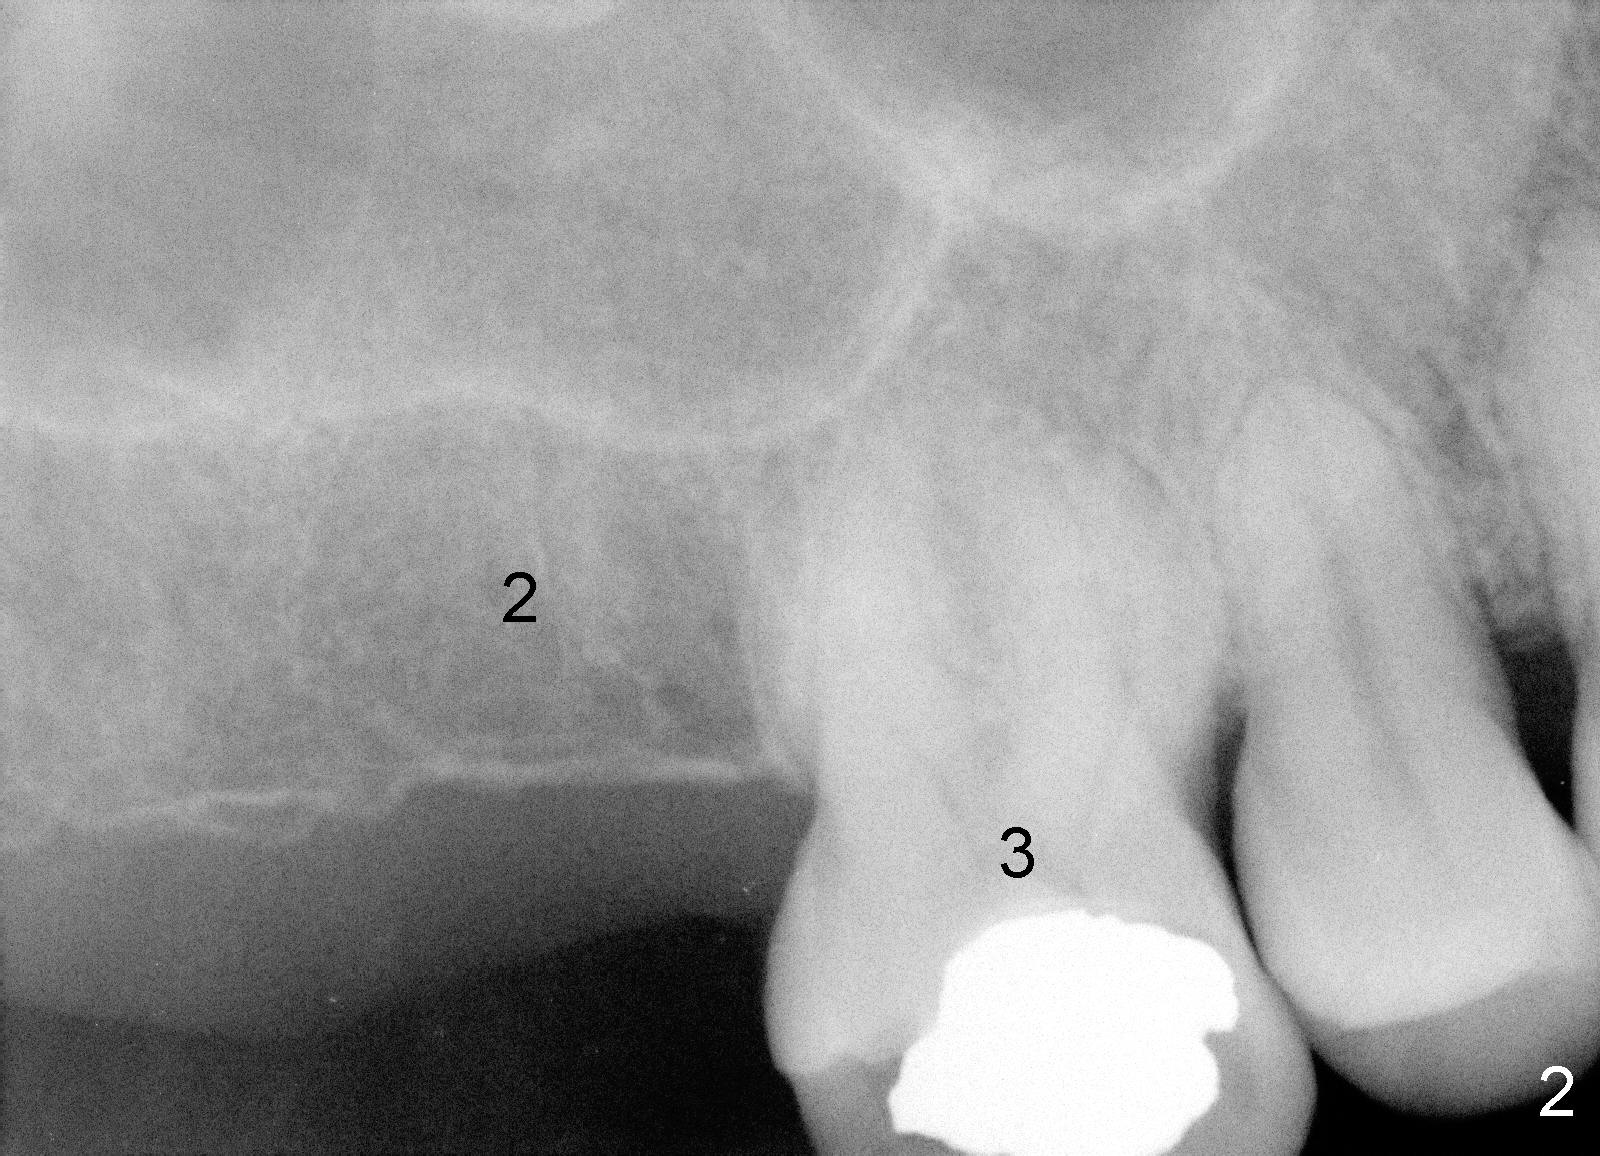

A 43-year-old lady develops tinnitus recently. Her primary care physician suspects that it is related to root canal therapy for the teeth #18 and 19 (Fig.1). Several more treatment is needed: extraction of #16 (Fig.1), RCT of #31 (Fig.1,3) and implant for #2 (Fig.1,2). Sinus lift and probably bone expansion may be required for #2 implant placement. Does usage of osteotomes worsen tinnitus, similar to occasional occurrence of vertigo after bone expansion?